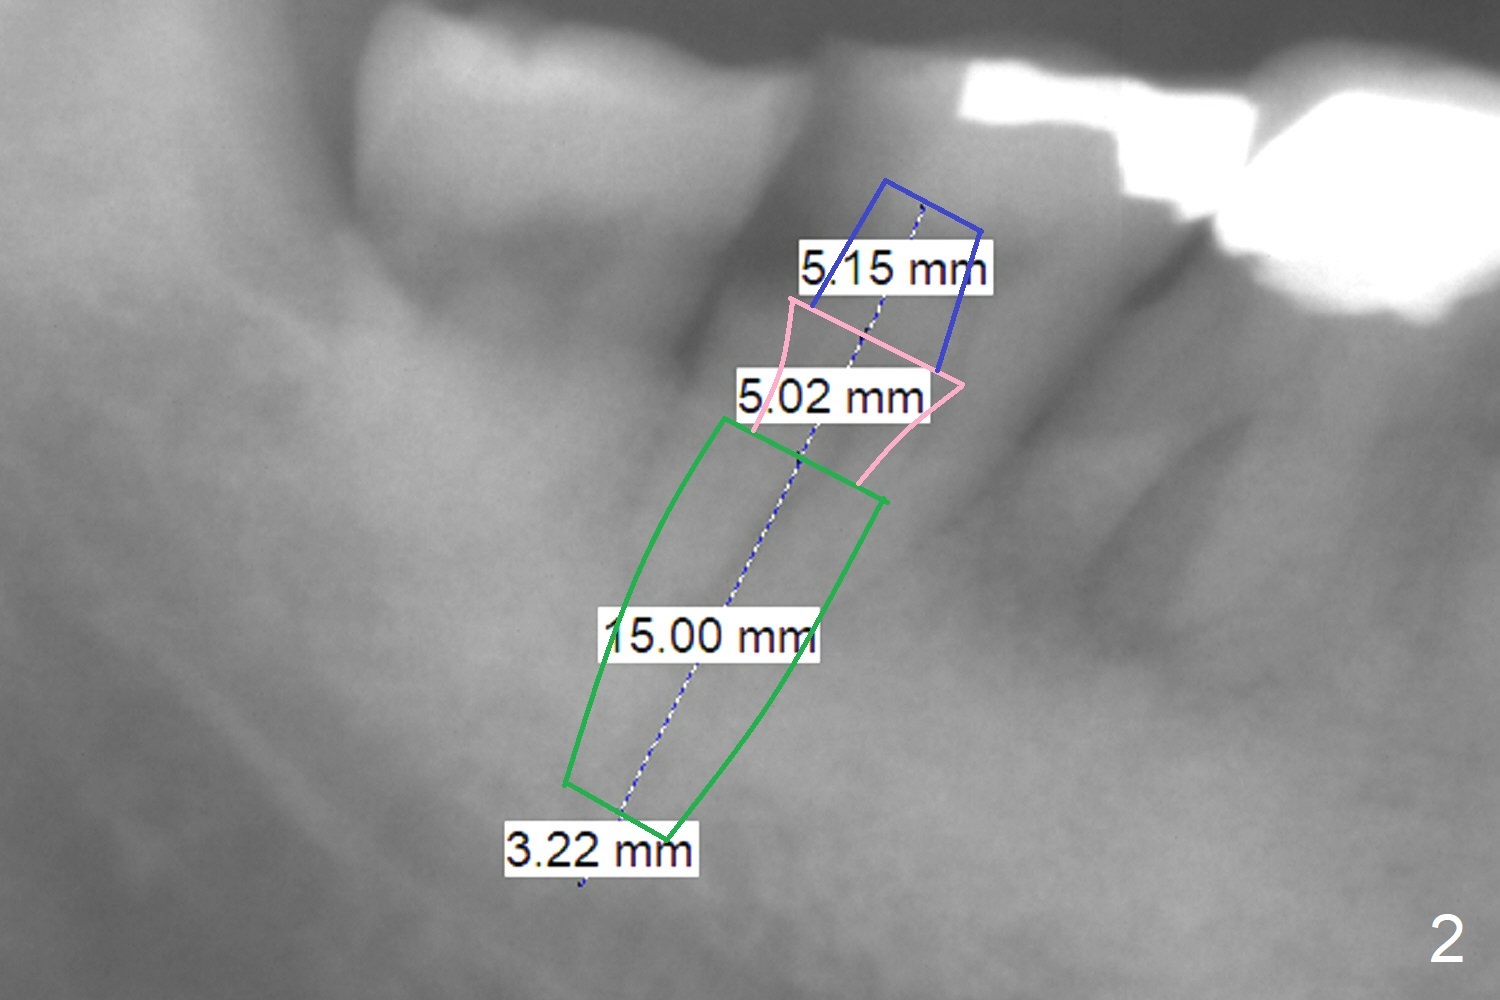

| Long Implant A 72-year-old man has DO subgingival caries (Fig.1 *). He prefers implant over RCT (Fig.2). The tooth #30 has deep pocket or an abscess distlbuccally. Cavitron scaling will be done. Return to